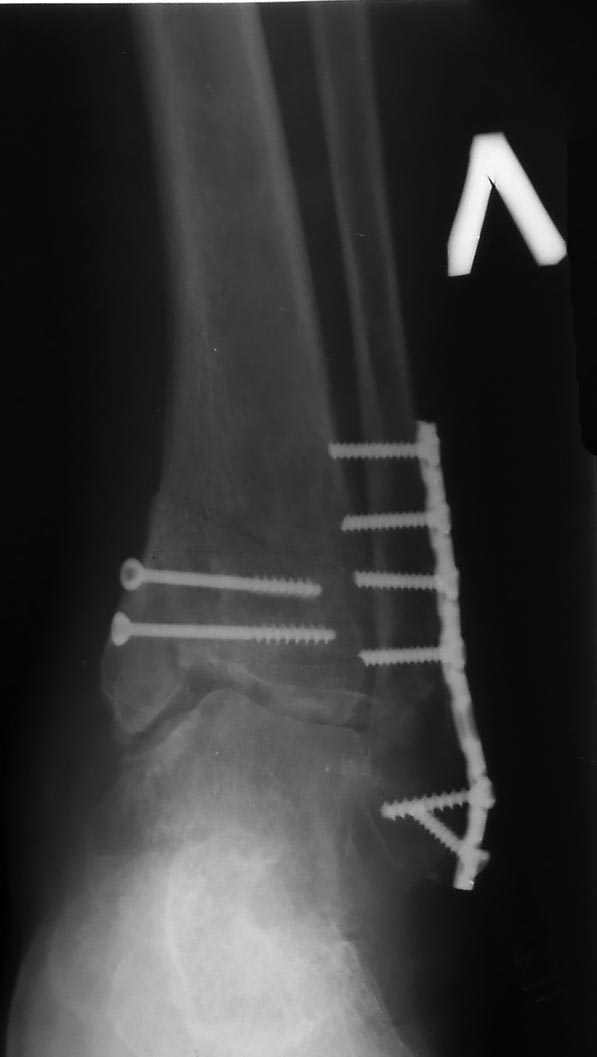

В приложении рентгенограмма первичная. После чего стала ясна сомнительность перелома пилона))) Перелом лодыжек с импрессией суставной поверхности большеберцовой кости в области внутренней лодыжки. На выполненном вчера КТ голеностопного сустава: в просвете сустава определяется клиновидной формы фрагмент костной плотности размером до 13,5х3,5 мм, находящийся в задне-латеральных отделах сустава.

Боковая проекция. Боковой проекции первичных рентгенограмм нет, утеряны больным.